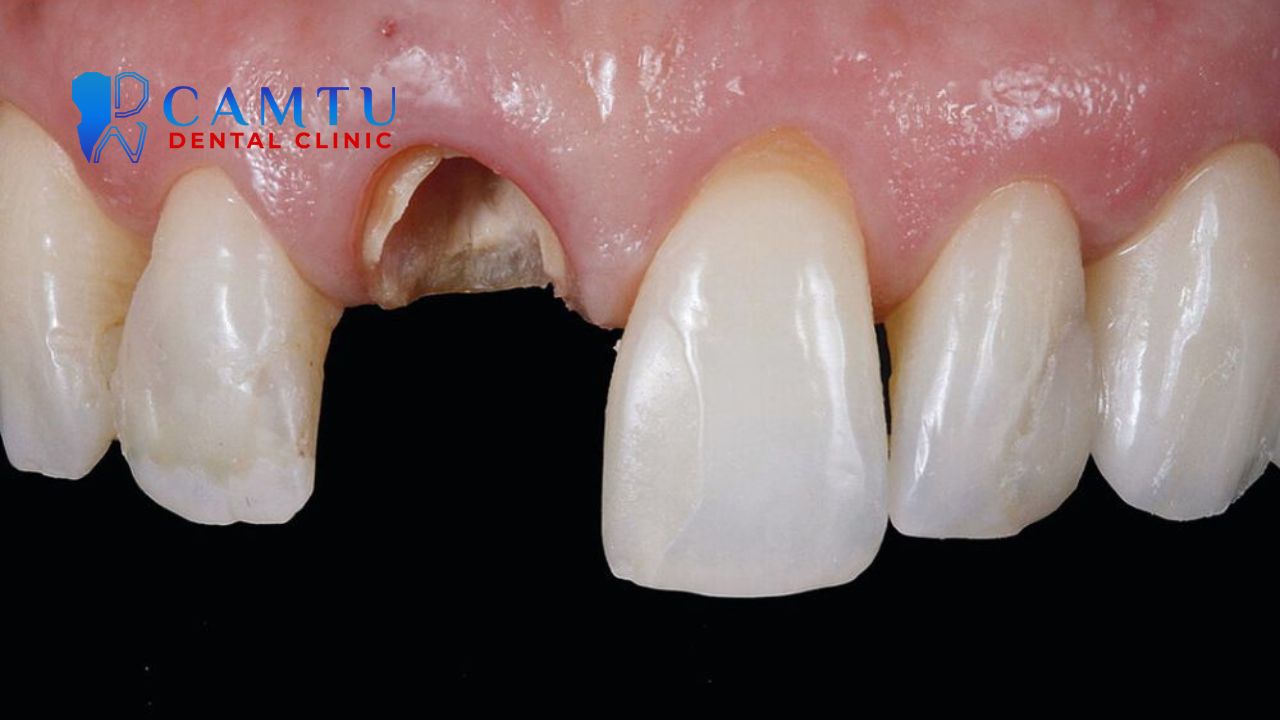

Ghép mô liên kết kết hợp vật liệu sinh học

Ghép mô liên kết kết hợp vật liệu sinh học là kỹ thuật điều trị các khuyết hổng mô mềm quanh implant đã tích hợp xương, đặc biệt là tình trạng nẻ mặt ngoài. Phương pháp này phối hợp giữa ghép mô liên kết và can thiệp phục hình - phẫu thuật nhằm tăng khả năng che phủ, cải thiện độ dày mô và che giấu màu xám của implant bên dưới. Quy trình đòi hỏi mô mềm phải được chuẩn bị và trưởng thành tốt trước phẫu thuật, đồng thời đảm bảo không có viêm quanh implant. Việc đặt mô ghép đúng vị trí, kết hợp vạt đưa về phía cổ và vật liệu sinh học hỗ trợ, giúp tăng nuôi dưỡng mạch máu, hạn chế co rút và mang lại hiệu quả thẩm mỹ ổn định, lâu dài.